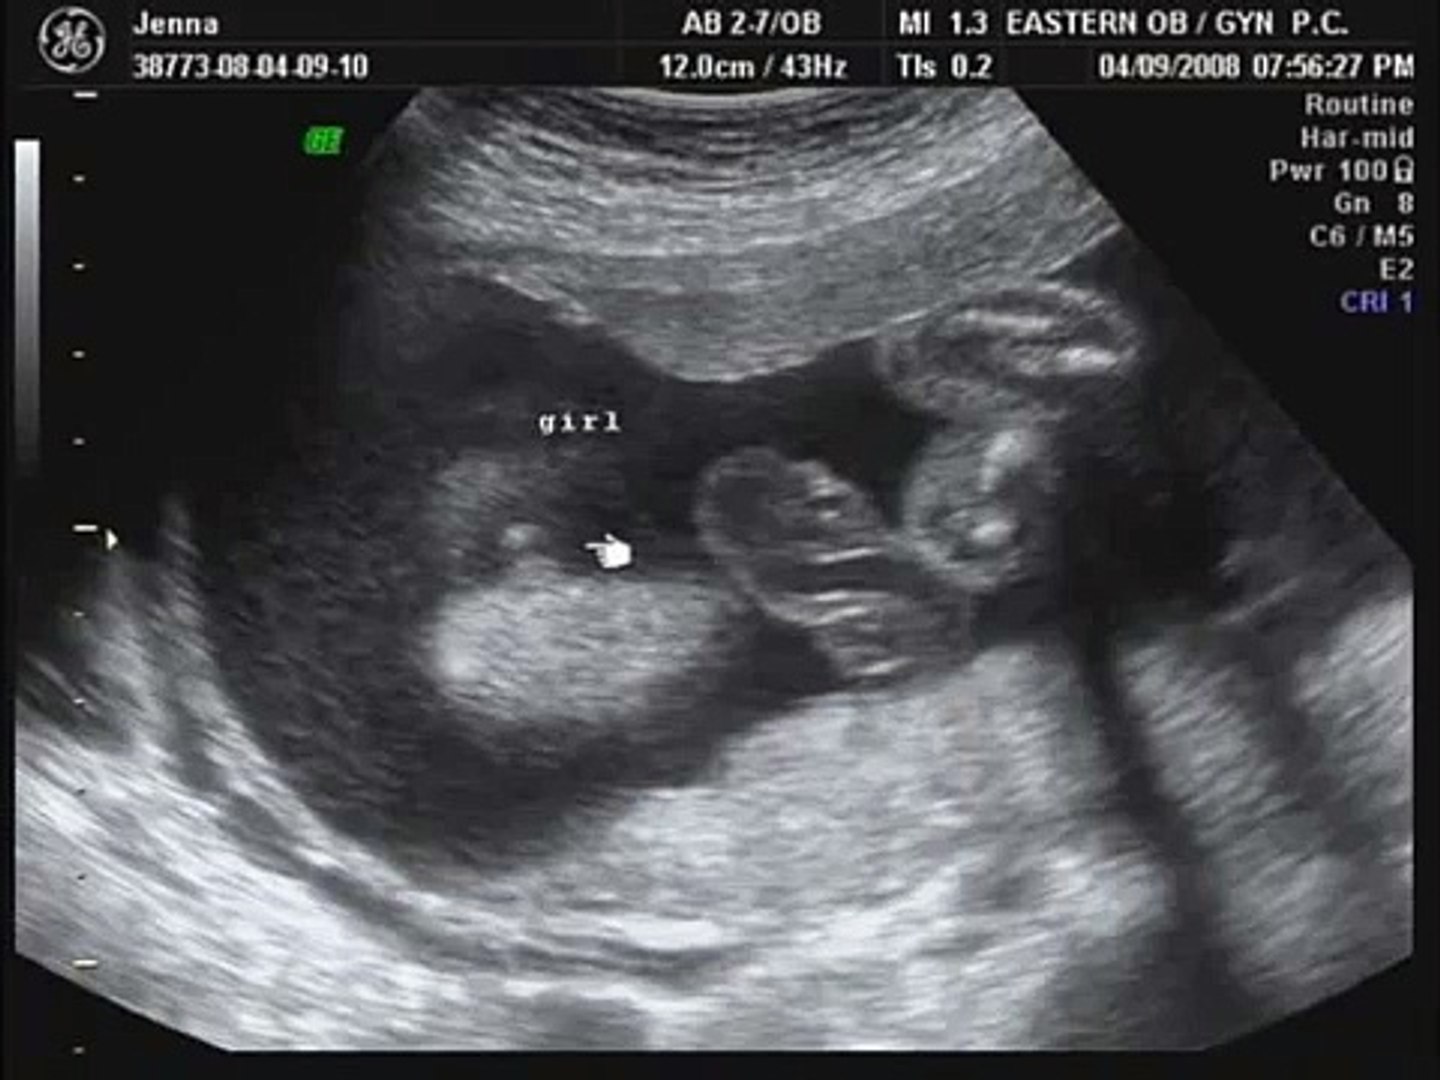

When you are in 24 weeks pregnancy, the baby's organs are fully formed and continue to mature and rapid eye movement can be noticed with 24 weeks pregnant ultrasound.

The ultrasound performed at 24 weeks pregnant period week will show the baby moving in the amniotic fluid. Also during this week, your baby's lungs start to develop. No sicknesses or any complications.

Also during this week, your baby's lungs start to develop. You're likely to have a glucose screening test to check for gestational diabetes. It's a big week for milestones as you near the end of the second trimester and look ahead to the final months of pregnancy. It grows at a rate of about 1 mm a day, starting at the 6th week of gestational age.